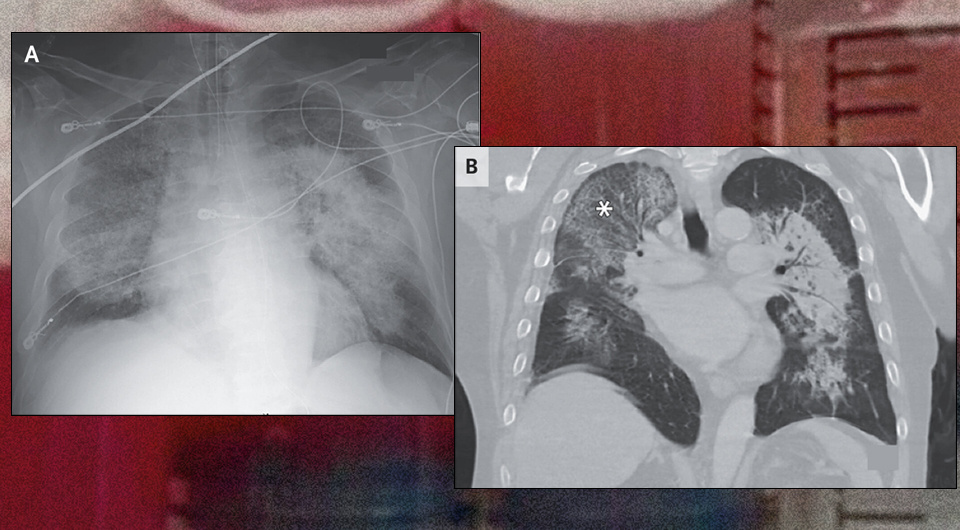

В неотложное отделение американской больницы поступил 57-летний мужчина с артериальной гипертензией и жалобами на прогрессирующую одышку в течение двух недель. Насыщение крови кислородом у него было 68 процентов (при норме от 95). При аускультации выслушивались влажные хрипы в обоих легких. Пациента при поступлении экстренно интубировали, на рентгенограмме грудной клетки визуализировались плотные прикорневые затемнения в обоих легких, расположенные по типу «крыльев летучей мыши». На компьютерной томограмме также были видны четко очерченные затемнения, достигающие субплевральных областей, в верхней доле правого легкого наблюдался симптом «булыжной мостовой» (затемнения по типу «матового стекла», наложенные на утолщение альвеолярных перегородок). В анализах отмечались выраженная анемия (гемоглобин 53 грамма на литр) и уровень креатинина 610 (при норме 62–115) микромоль на литр, а также гематурия и протеинурия. Врач Айрин Ли (Irene Lee) из Бэйлоровского медицинского колледжа описала этот

В неотложное отделение американской больницы поступил 57-летний мужчина с артериальной гипертензией и жалобами на прогрессирующую одышку в течение двух недель. Насыщение крови кислородом у него было 68 процентов (при норме от 95). При аускультации выслушивались влажные хрипы в обоих легких. Пациента при поступлении экстренно интубировали, на рентгенограмме грудной клетки визуализировались плотные прикорневые затемнения в обоих легких, расположенные по типу «крыльев летучей мыши». На компьютерной томограмме также были видны четко очерченные затемнения, достигающие субплевральных областей, в верхней доле правого легкого наблюдался симптом «булыжной мостовой» (затемнения по типу «матового стекла», наложенные на утолщение альвеолярных перегородок). В анализах отмечались выраженная анемия (гемоглобин 53 грамма на литр) и уровень креатинина 610 (при норме 62–115) микромоль на литр, а также гематурия и протеинурия. Врач Айрин Ли (Irene Lee) из Бэйлоровского медицинского колледжа описала этот случай в The New England Journal of Medicine.

На основании клинической картины и данных обследования у пациента заподозрили диффузное альвеолярное кровотечение. Его подтвердил повторный бронхоальвеолярный лаваж, при котором были получены аликвоты жидкости с прогрессирующим нарастанием содержания крови. Для уточнения диагноза мужчине выполнили анализ на антинейтрофильные цитоплазматические антитела (АНЦА) и биопсию почек. Они позволили определить АНЦА-ассоциированный васкулит — редкое гетерогенное аутоиммунное заболевание, которое характеризуется некротизирующим воспалением мелких сосудов и разнообразными клиническими проявлениями (чаще со стороны легких и почек). Пациенту назначили глюкокортикоиды, циклофосфамид, плазмообмен и гемодиализ в постоянном режиме, однако несмотря на проводимое лечение он скончался через 23 дня после поступления.